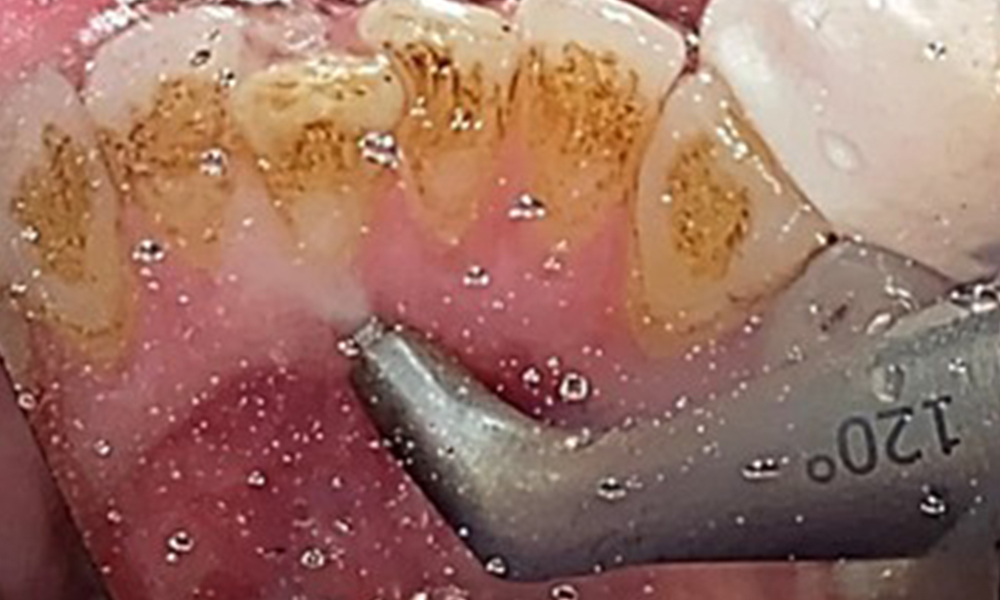

En raison d'un état de santé général par ailleurs favorable, les besoins déterminés lors de l'examen intra-oral seront déterminants pour le traitement. Il sera essentiel de déterminer périodiquement les profondeurs de sondage. Le saignement gingival diminue chez les fumeurs, c'est pourquoi le diagnostic clinique de la parodontite ne peut se faire que par sondage (Fig. 7). En se concentrant exclusivement sur la détermination des indices de saignement, on risque d'occulter une parodontite ou une gingivite existante. (5)

L'objectif serait de contrôler le risque de maladie en éliminant le biofilm supra-gingival et sous-gingival. Les instruments peuvent être sélectionnés en fonction des besoins du patient. Tout d'abord, le tartre et les concrétions doivent être éliminés à l'aide d'instruments ultrasoniques et/ou manuels (Fig. 10).